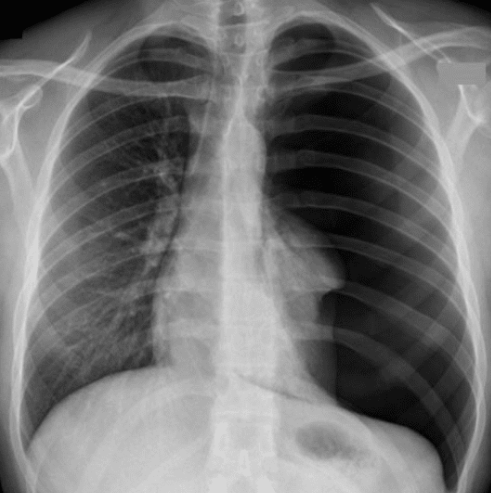

X線写真は、患者さんがこちら側(読影者側)を向いているビューなので、この画像の左側=患者さんの右肺。こちらは肺血管が末梢まで追えており正常です。

一方、画像の右側=患者さんの左肺。 こちらは肺血管の模様が見えず、ほぼ黒いので左肺が虚脱して空気が貯留していることを意味します。

これで左気胸と判断できます。

ほぼ完全に虚脱しているため、重症度は 3度になります。

さらに心臓は本来の位置よりもこの画像の左方向(=患者さんの右側)に偏位しており、本来なら心音はやや左胸(この画像だと右側)で聴取されるはずが、本症例では心音の位置が中央にずれていた。